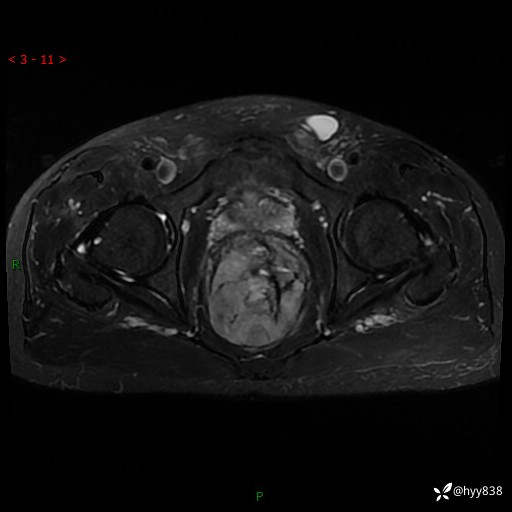

盆腔MRI平扫